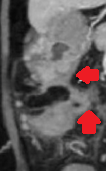

Contrast-enhanced CT of the abdomen, revealed a grossly distended stomach with mild diffuse thickening of its wall (red arrow)